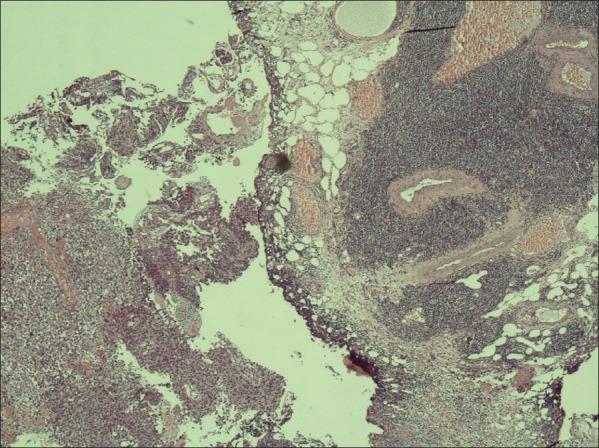

T-lymphocytic infiltration near the tumor site is an expected immune response in bladder cancers. However, reports of patients with bladder cancer exhibiting small lymphocytic infiltration of the bladder tissue are very rare in the literature. Here, the patient was presented to our group with hematuria, but subsequently diagnosed as exhibiting invasive bladder cancer and chronic lymphocytic leukemia with suspicious lymphocytic infiltration in a transurethral resection specimen. This case emphasizes the importance of lymphocytic infiltration's nature near urothelial carcinoma.

肿瘤部位附近的T淋巴细胞浸润是膀胱癌中预期的免疫反应。然而,文献中关于膀胱癌患者膀胱组织淋巴细胞浸润较少的报道非常罕见。在此,该患者因血尿前来我院就诊,但随后经诊断为浸润性膀胱癌和慢性淋巴细胞白血病,经尿道切除标本中可见可疑的淋巴细胞浸润。该病例强调了尿路上皮癌附近淋巴细胞浸润性质的重要性。